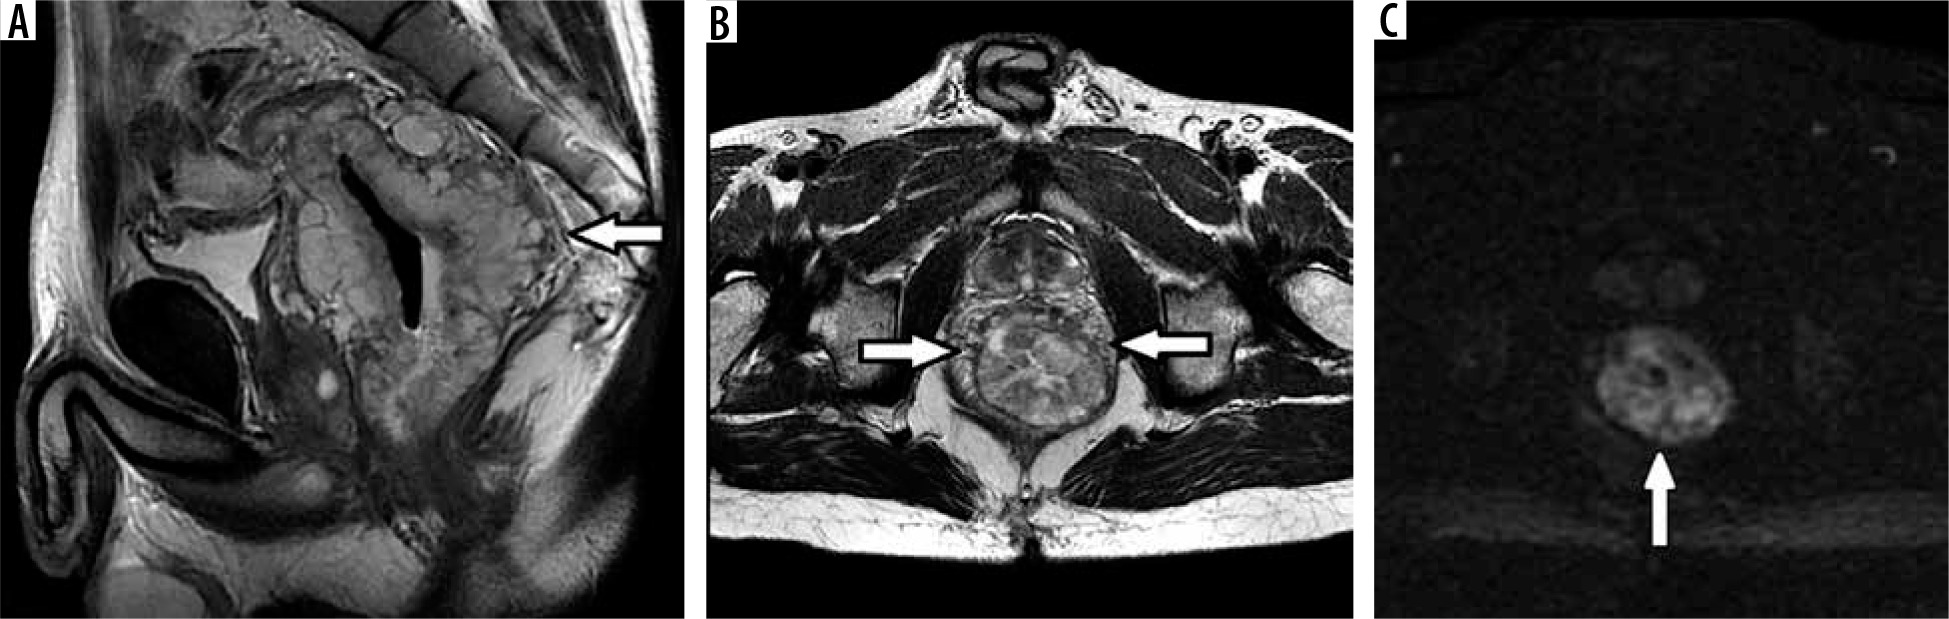

Figure 2

Rectal well-differentiated mucinous adenocarcinoma G1. High signal intensity of circular rectal tumour (arrows) with invasion of all layers of the rectal wall in T2 FSE sagittal (A) and axial (B) images. DWI with b = 1000 (C) shows restricted diffusion within the tumour tissue (arrow), ADC = 1.7 mm2\s × 10-3